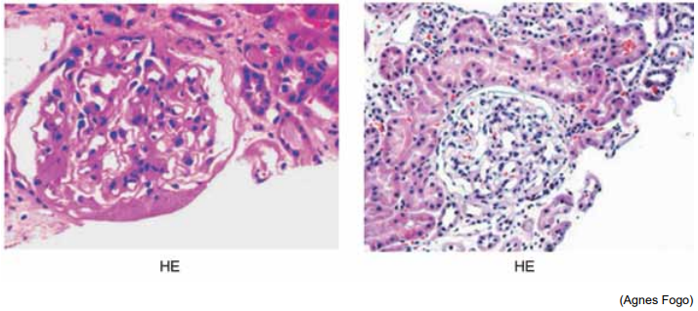

Observe a figura a seguir, na qual a microscopia óptica representa nefrite lúpica e sua classificação de acordo com ISN/RPS (International Society of Nephrology e Renal Pathology Society):

Com base nesse contexto, qual o tratamento preconizado na fase de indução?